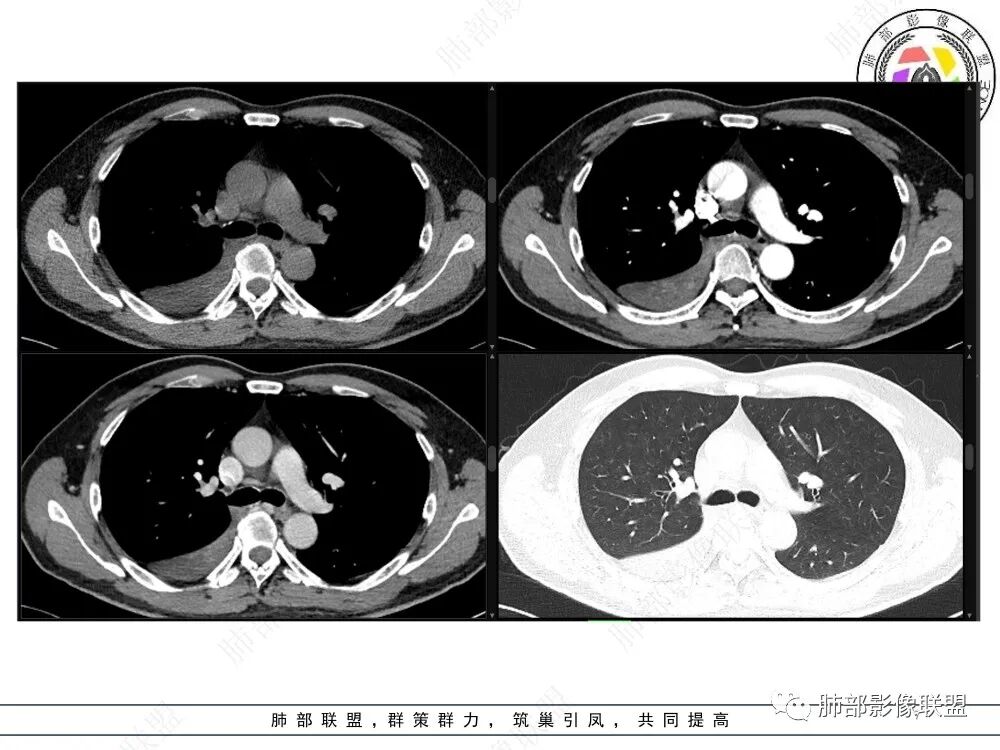

中央型肿瘤pk周围型肿瘤  。壮年男性,热咳一周伴气喘,中性白细胞升高,临床是个感染过程。支持中央型病变的证据:1  肺门明显强化结节 2 横s征  3 支气管粘液栓  4 主支气管变窄,似见冰山征      支持周围型病变:1 按叶段塑形  2 血管造影征  3 病灶内弥漫高强化  4 周围伴磨玻璃灶,但境界不清继发感染?误吸?综合 中央型肿瘤可能大:类癌》鳞癌

病灶主要在后、外基底段

长轴、支气管、血管是观察的重点

这就需要重建

中间段支气管

基底干是外侧朝腔内压迫?还是外侧壁占位突入腔内?

这是肺门淋巴结压迫、侵犯支气管导致堵塞?还是腔内本身肿瘤?

远端支气管是粘液栓

这个问题关系到诊断的问题

首先血管未见明显侵犯、移位,提示病灶:炎性;肿瘤:外朝内——含粘液类腺癌(肺门淋巴结转移),腔内肿瘤(鳞癌、腺癌、类癌、小细胞、粘液表皮等)

尹芳老师发dicom格式的给我了,我重建一下

冠状位重建有钻缝的感觉

南边:

粘液腺不符合

粘液腺是外围朝内推移的

不应该近端腔内结节强化明显

我再发一些图

这是源头

这些如果单纯不张肯定强化明显